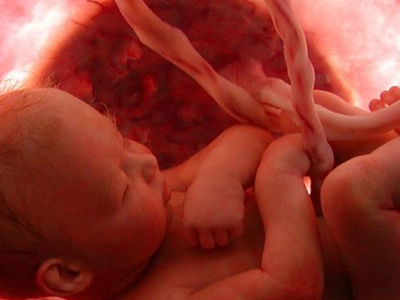

Τα έμβρυα όχι μόνο έχουν λόξυγγα, καταπίνουν ή τεντώνονται μέσα στη μήτρα της εγκύου μητέρας τους, αλλά, όπως ανακαλύπτεται τώρα, χασμουριούνται κιόλας. Μέχρι σήμερα υπήρχε διαφωνία των επιστημόνων για το εάν τα αγέννητα μωρά χασμουριούνται ή απλώς ανοίγουν το στόμα τους, αλλά μία νέα έρευνα έρχεται να βεβαιώσει ότι πολύ συχνά ισχύει το πρώτο.

Οι ερευνητές των βρετανικών πανεπιστημίων του Ντέραμ και του Λάνκαστερ, με επικεφαλής την ψυχολόγο Νάτζα Ράισλαντ, που έκαναν τη σχετική δημοσίευση στο περιοδικό «PLoS ONE», σύμφωνα με το πρακτορείο Reuters, μελέτησαν 20λεπτης διάρκειας βιντεοσκοπημένους υπέρηχους 15 υγιών εμβρύων (οκτώ κοριτσιών και επτά αγοριών), που βρίσκονταν μεταξύ της 24ης και της 36ης εβδομάδας της κύησης. Οι επιστήμονες διαπίστωσαν ότι και τα δύο φύλα χασμουριούνται συχνά, ενώ μετά την 28η εβδομάδα παρατηρείται σταθερή μείωση του χασμουρητού.

Με βάση τη διάρκεια που το έμβρυο μέσα στη μήτρα κρατά ανοικτό το στόμα του και πόσο αργά το ανοίγει, εκτιμάται ότι πάνω από τις μισές φορές χασμουριέται. Αν και η λειτουργία και η σημασία του χασμουρητού παραμένουν άγνωστες, οι επιστήμονες θεωρούν ότι είναι μια φυσική διαδικασία που σχετίζεται με την ανάπτυξη του παιδιού και έτσι θα μπορούσε να αποτελέσει ακόμα έναν δείκτη για την υγεία του εμβρύου. «Αντίθετα με εμάς, τα έμβρυα δεν “κολλάνε” το χασμουρητό από άλλους, ούτε χασμουριούνται επειδή νυστάζουν. Μάλλον, η συχνότητα του χασμουρητού τους στη μήτρα σχετίζεται με την ωρίμανση του εγκεφάλου και του κεντρικού νευρικού συστήματος κατά την κύηση» δήλωσε η Ράισλαντ, αν και, όπως είπε, χρειάζονται περαιτέρω έρευνες πάνω στο ζήτημα.

Πέρυσι, η ίδια ερευνητική ομάδα είχε ανακαλύψει σε δύο έμβρυα μέσα στη μήτρα πολύπλοκες εκφράσεις του προσώπου, σαν το γέλιο και το κλάμα, μεταξύ της 24ης και της 35ης εβδομάδας της κύησης.